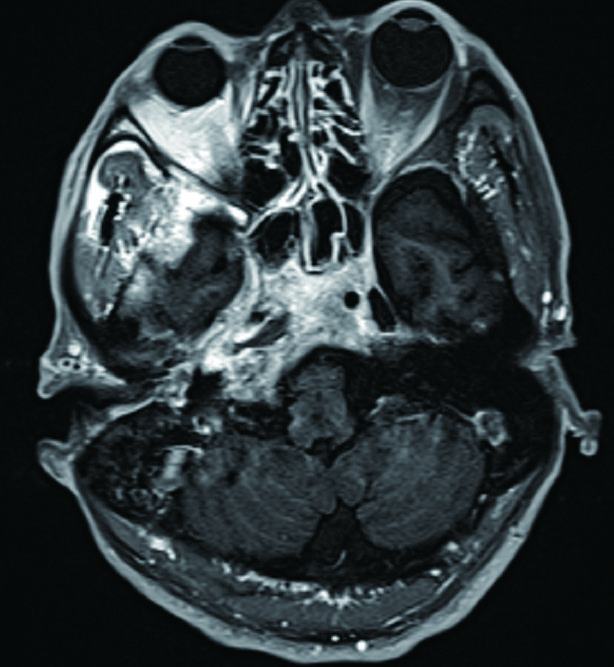

1 资料与方法病例1,患者男性,66岁,因头痛3周,复视1周入院。患者3周前起右侧太阳穴针刺样疼痛,影响睡眠。2周前出现咽痛鼻塞流涕及双耳听力下降,伴有右侧额部皮肤红疹,上述症状在当地医院治疗后减轻。1周前出现复视,当地医院治疗后症状无好转,诊断:颅内感染,多颅神经麻痹转来本院急诊。查体:神清,面部可见散在淡色丘疹,以右侧前额为主,右眼外展受限,面部痛触觉无殊,四肢肌力5级,病理反射阴性。脑脊液生化常规示:潘氏试验阳性,有核细胞970/μL;血沉28.00 mm/h,C反应蛋白14.1 mg/L。增强头颅MR提示两侧海绵窦增粗增宽,考虑炎症,并见双侧筛窦上颌窦蝶窦炎(图 1)。予头孢曲松钠2.0 g静脉注射抗感染治疗。治疗2周后头痛明显减轻,但复视症状无好转。复查血常规正常,C反应蛋白正常范围,血沉28.00 mm/h,脑脊液生化及常规正常范围。复查头颅增强MR提示病变范围较前无缩小。鼻窦CT提示双侧蝶窦炎症较前加重(图 2)。建议患者行鼻内镜下蝶窦手术。患者自觉症状减轻拒绝手术,要求出院。出院后在外院继续头孢曲松钠抗感染治疗。治疗10 d后因头痛复视症状无改善,并出现面颊部感觉减退再次入院。入院后查血常规,C反应蛋白正常,血沉28.00 mm/h,脑脊液潘氏试验阳性,细胞数量继续减少至60/μL。继续抗感染治疗。再次头颅MR及鼻窦CT复查提示海绵窦及蝶窦内病变较前范围增大(图 3),经多学科讨论,转本科行视频内镜下双侧蝶窦开放术。术后第三天鼻腔填塞物完全抽除后头痛症状明显缓解,术后6 d出院,头痛症状消失,复视仍存,出院后继续抗感染治疗,定期门诊复诊,术后6个月,复视症状消失。

| 图 2 左侧蝶窦密度增高影,右侧窦内密度增高影,窦内含气 |